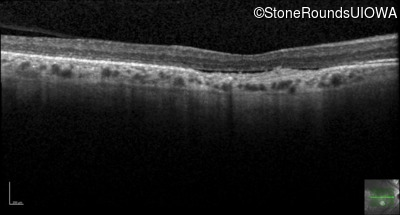

Optical Coherence Tomography - Left - 20/100

Exemplar / OCT Stack